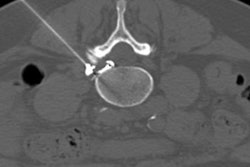

When reporting presigning imaging, it is important to identify small and often asymptomatic meniscal tears, particularly in the load-bearing regions of the meniscus. As in this case of a tear of the posterior horn of the lateral meniscus seen on presigning imaging (above), these tears can extend and displace, producing pain and locking requiring resection (below). All images courtesy of Dr. Andrew Dunn.The first MRI scan of a new player provides the baseline image to document the current status of commonly injured body parts, and if imaging identifies abnormalities that might be unstable or progressive, such as an osteochondral knee lesion, then this may influence transfer negotiations, Dunn noted. The MRI scan also serves as a comparison for potential future injuries, which can be helpful to the radiologist, particularly if preclinical abnormalities were depicted in the original presigning medical exam.

Knee protocols include sagittal, coronal, and axial combination of high-resolution proton density fat-saturated and proton density sequences of no greater than 3-mm slice thickness. Dunn underlined that small degenerative tears in the anterior horn of the lateral meniscus may be a common subclinical finding and do not usually raise concerns for the referring clinician. However, larger, potentially displaceable tears of the posterior horns could progress more suddenly, requiring arthroscopic repair or resection and affecting an athlete's playing time.

Images often depict chronic, small, healed tears that are clinically stable. "These demonstrate intermediate signal on T2 or intermediate weighted MR sequences, and should not be misread as active tears," he wrote.